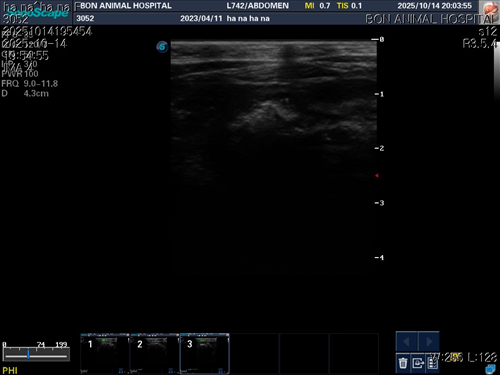

10월 10일 포도를 토해논후로 식욕저하 기력저하가 있어서 동물병원에 방문해서 엑스레이를 찍었는데 우선 지켜보자는 말과 소화제처방과 주사를 맞고 집왔습니다 그 후로도 안먹어서 12일에 동물병원에가서 혈액검사도 하고 수액도 맞았습니다 췌장쪽 수치가 좀 높아서 췌장쪽만 다시 검사했는데 수치는 괜찮았습니다 식욕촉진이랑 소화제처방 받아서 먹이는데 식욕저하도 여전하고 기력이 좀 없고 10일부터 14일까지 대변을 못보고있어서 14일에 병원에 가서 엑스레이랑 초음파를 했는데 장폐색일수도 있다는 말을 들었습니다 초음파상으로는 소장쪽 이물이 의심된다고 하셨어요ㅠ